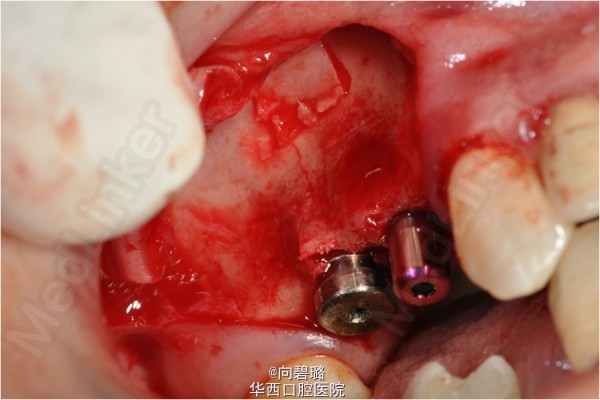

诊断:牙列缺损 治疗计划:上颌窦外提升术。(每一颗种植体植入前,都进行了精确的共振频率分析作为种植体稳定系数的评价。)

上颌窦提升术已经成为一个世人公认有效弥补骨量减少患者的方法。自1970年以来,各种有助于骨再生的临床研究被开展,研究方面多半是关于上颌窦提升方面和囊腔填充两个方面的。本例就采用了上颌窦外提升法顺利为患者植入种植体。